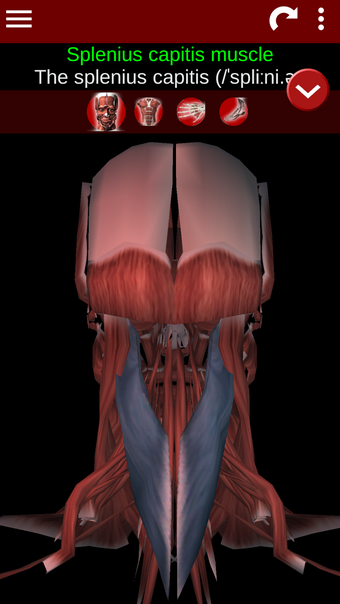

Esta herramienta educativa proporciona una descripción de cada músculo del cuerpo humano, así como un modelo tridimensional del sistema muscular. Con sólo tocar con el dedo, la aplicación revelará la información pertinente.

Los usuarios pueden hacer zoom sobre el músculo, así como elegir si ocultar o mostrar los datos. La orientación puede ser horizontal o vertical, según convenga más.